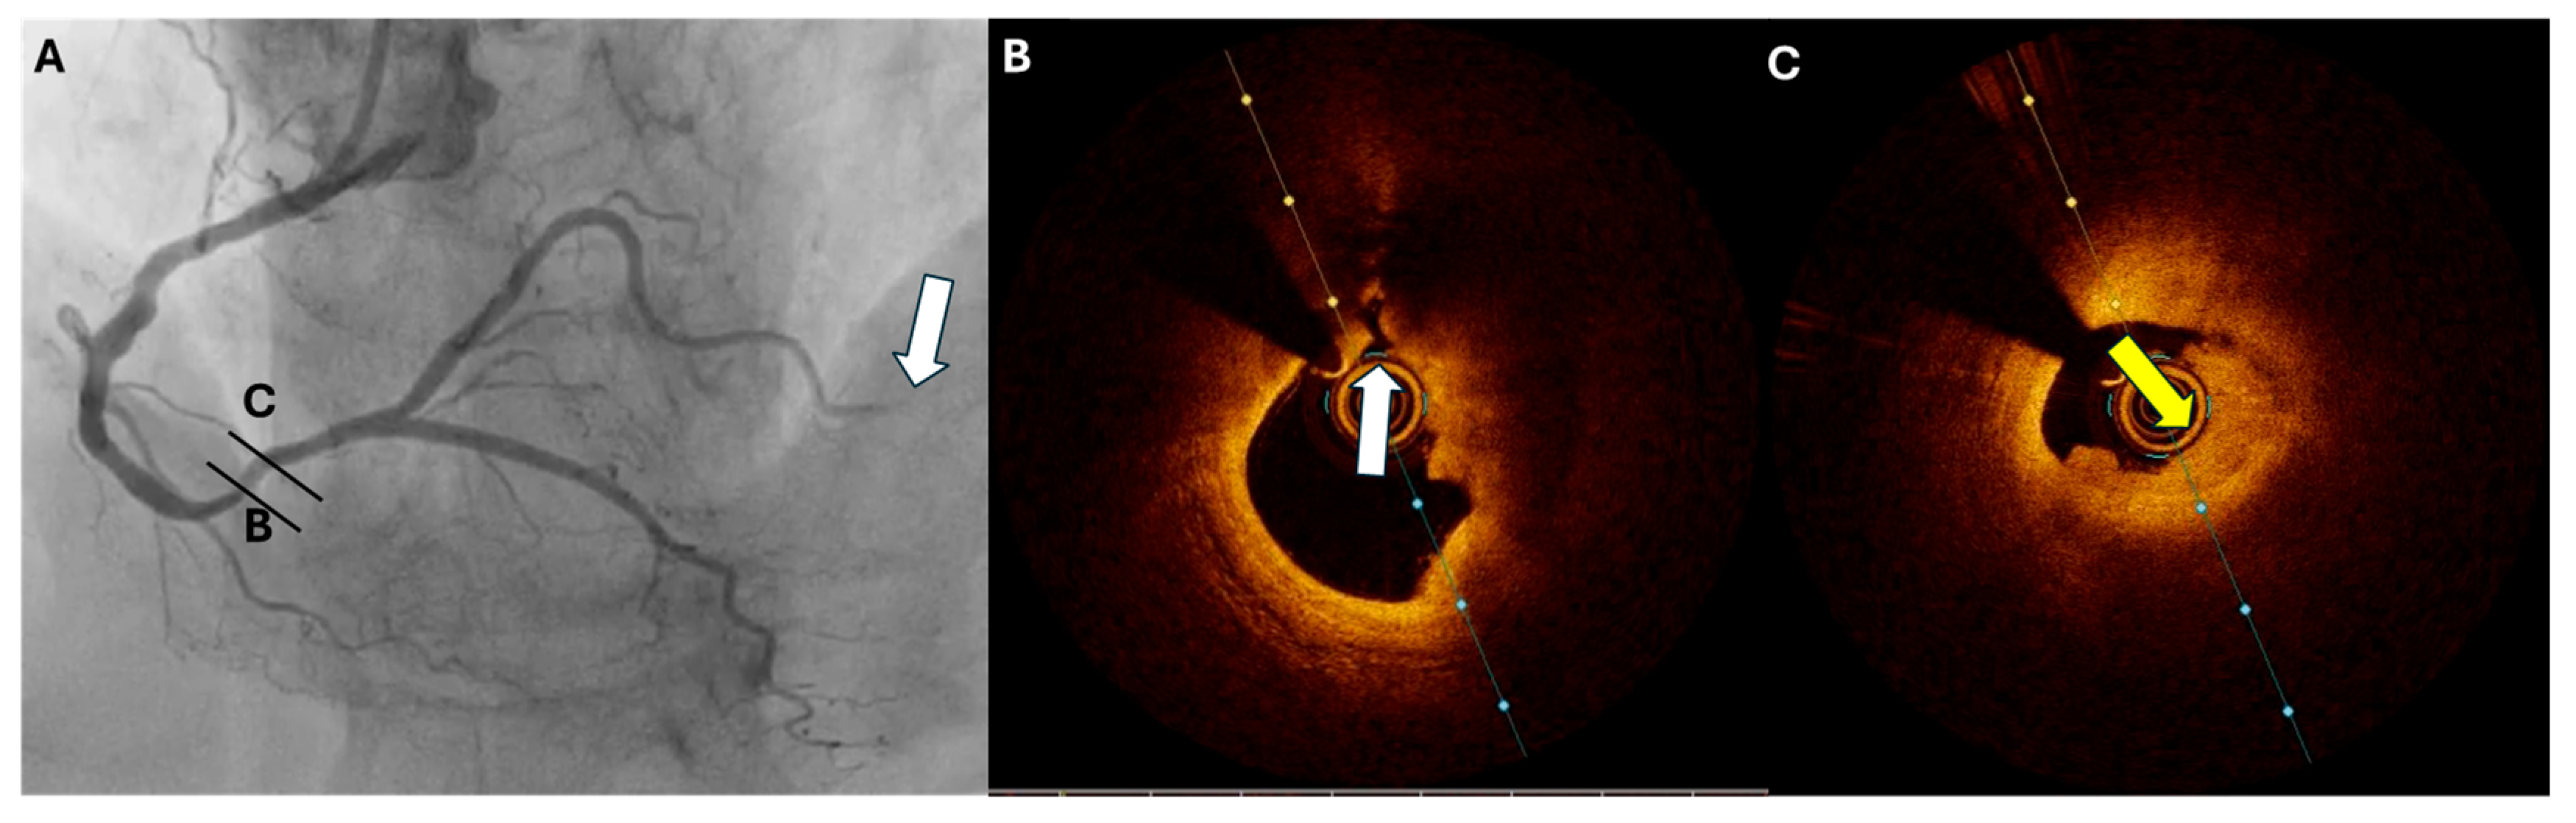

3.3. Calcific Nodules